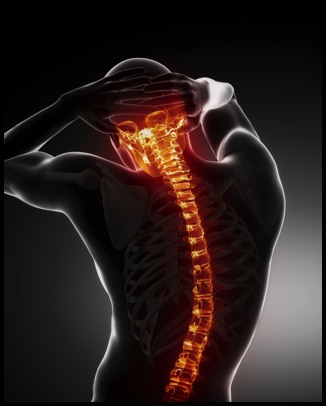

Spinal fusion surgery is performed to fuse together two or more vertebrae so that they heal into a single, solid bone. This is done to eliminate painful motion or to restore stability to the spine. This type of spine surgery is more commonly performed on your low back and neck. There are multiple methods for spinal fusion which will be discuss with you by your physician. Physical therapy after spinal fusion will help decrease pain as you recover as well as address abdominal weakness following your surgery.

For more information regarding a spinal fusion visit: https://orthoinfo.aaos.org/en/treatment/spinal-fusion/